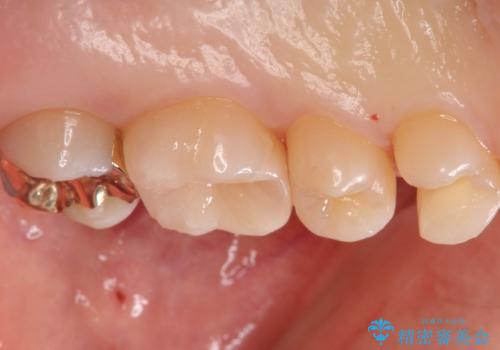

歯と歯の間の虫歯 インレーでの治療(セラミック・ゴールド)

- 銀歯のやり替えと虫歯の治療をご希望で来院された患者様です。

一番奥の歯は外から見えにくい部分であるためゴールドインレーで修復します。

その他はセラミックインレーで修復します。

- 左上46:セラミックインレー/77,000円×2 左上7:ゴールドインレー/77,000円×1費用は治療当時の料金となります

噛みしめの強い方や、外から見えないような部分では、割れる心配のないゴールドインレーをおすすめします。